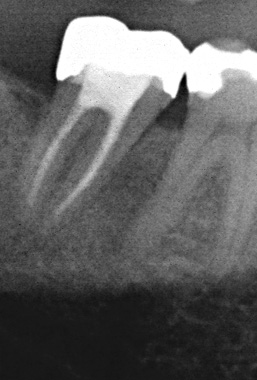

Röntgenologischer Ausgangsbefund

Röntgenologischer Ausgangsbefund im August 1996 bei Zahn 44 mit chronisch apikaler Parodontitis; Zustand vor umfangreicher ZE-Neuversorgung. Erste Therapie der Wahl ist in diesem Fall immer die konventionelle Wurzelkanalbehandlung ohne primär chirurgische Intervention